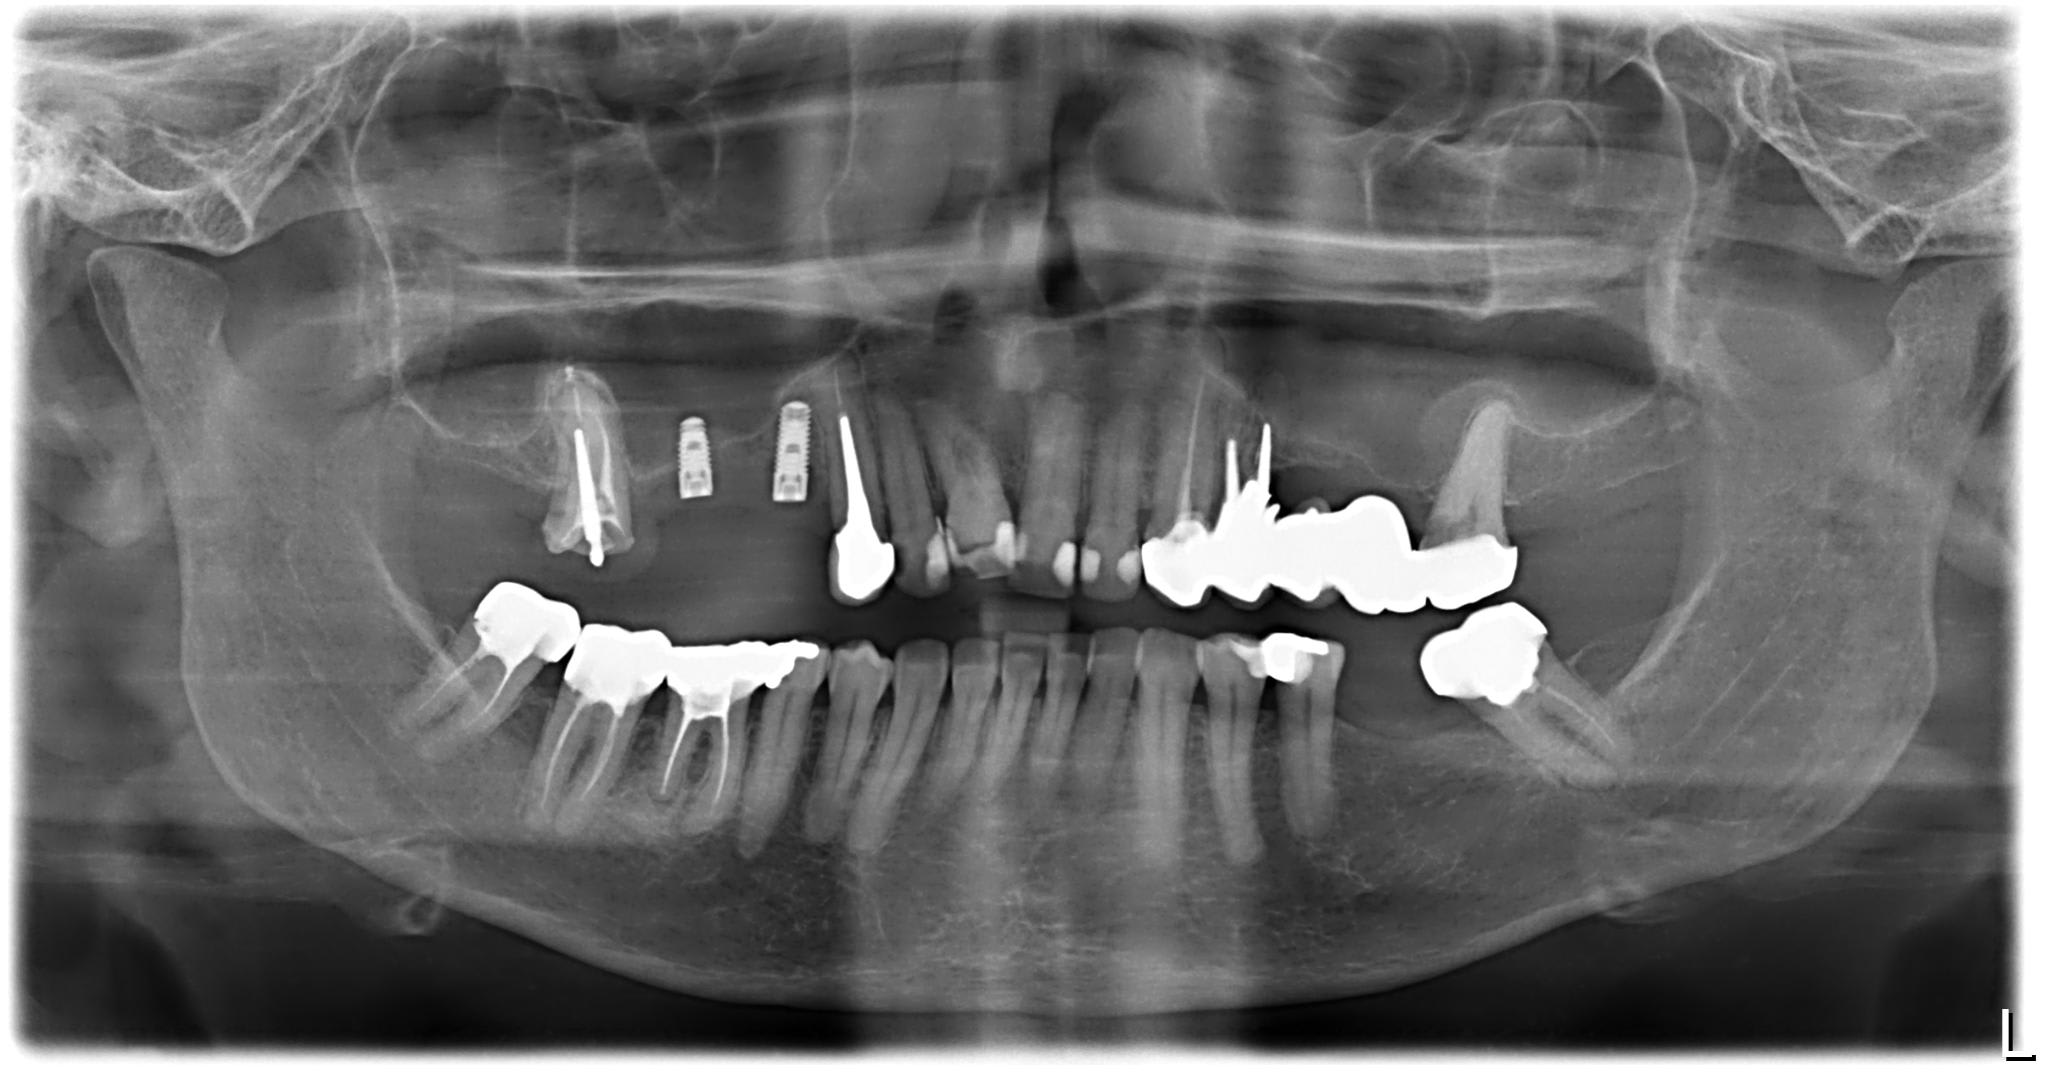

le praticien posait du Zimmer.

Sur 14, un TSV?

ouaip

16 aussi

L'endo sur 12 est vraiment pas terrible et tu n'aurais pas une resorption radiculaire sur 11 ?